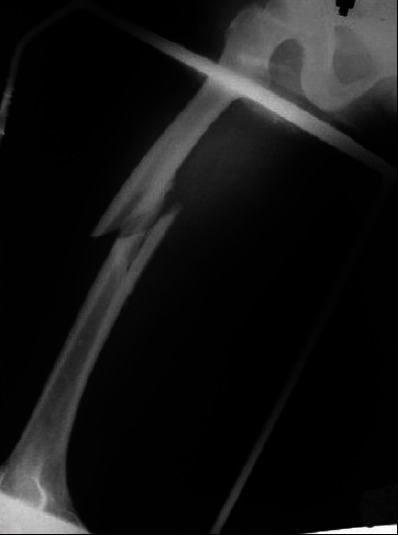

Management of maternofetal emergency in shock with fracture of femur.